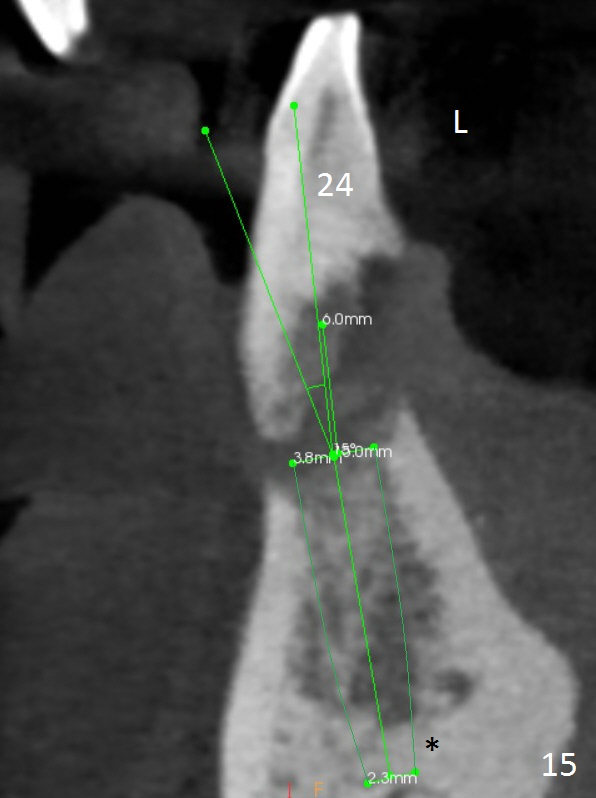

Class II Division II malocclusion (Fig.2,6) will make it difficult to restore #23-26 implant-supported FPD. Although the teeth #7-10 may need to be replaced later (Fig.7,8), enameloplasty will be conducted for #7-10 (Fig.9 white area; Fig.12 black circles (gross reduction)) prior to #23-26 extraction and implant placement (Fig.10). To be flexible in restoration (angulation) and possible future hybrid denture, 2-piece narrow implants will be placed (3.0 or 3.3 mm) instead of 1-piece ones. In fact CBCT shows that the narrowest regular implant (3.8 mm) can be placed in the lower anterior region (Fig.13-15).